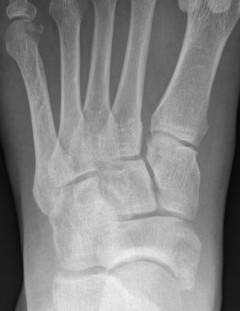

X-ray

Subtle widening of the medial cuneiform - 2nd metarsal distance, and the inter-metatarsal distance

Widening of the medial cuneiform - 2nd metatarsal distance, inter-metatarsal diastasis, fleck sign, possibly increased inter-cuneiform distance

Widening of the medial cuneiform - 2nd metatarsal distance, inter-metatarsal diastasis, fleck sign, increased inter-cuneiform distance